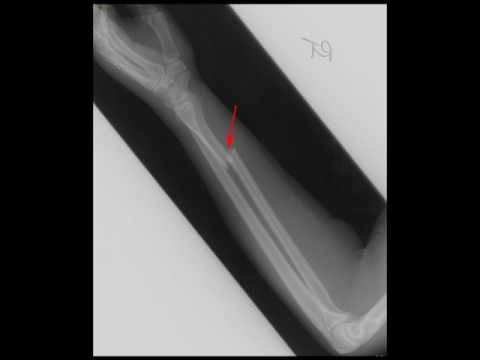

Galeazzi Fracture

Galeazzi Fracture - Fracture of the Radius Bone 🦴- Orthopedic surgery

Galeazzi Fracture Dislocation - Orthopedics for Medical Students

Galeazzi Fracture Dislocation: Clinical Features, Treatment and Complications